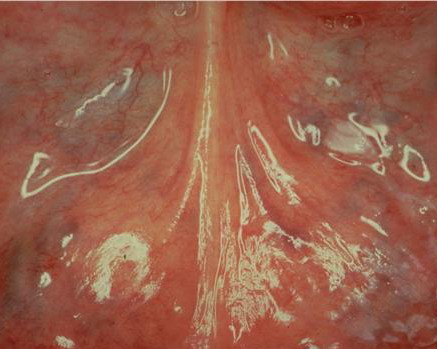

Leucoplakia Praecancerosa = الطلاوة ماقبل السرطانية